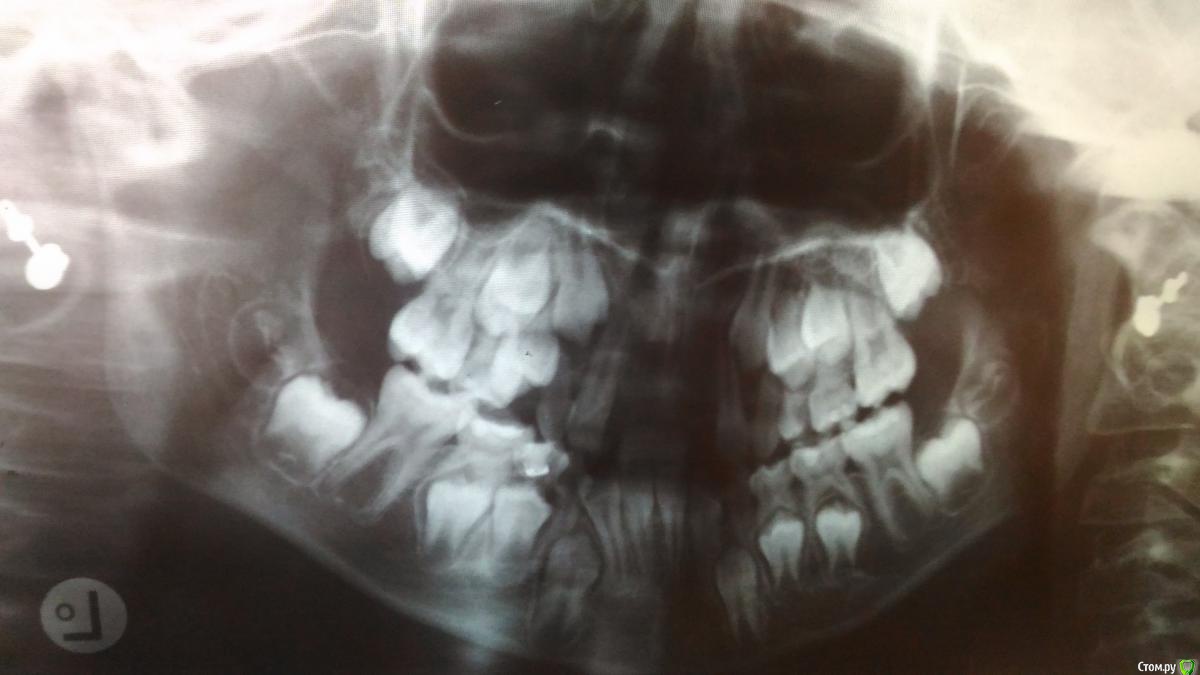

KaLiNa Опубликовано 22 июля, 2017 Автор Поделиться Опубликовано 22 июля, 2017 Уважаемые доктора, добрый вечер! Спустя месяц после травмы ребенку изготовлен ЧСП, выкладываю панорамный снимок и фото, а также фото зубов до травмы(крупные), а в протезе изготовлены гораздо меньше...все ли сделано правильно? Ссылка на комментарий

Bier Опубликовано 24 июля, 2017 Поделиться Опубликовано 24 июля, 2017 еще бы фото девочки с протезом, но вообще все верно. С таким протезом пусть живет до прорезывания всех зубов, потом брекеты ( к брекетам тоже можно имитацию зубов приклеить). Ну и потом уже имплантация. Ссылка на комментарий